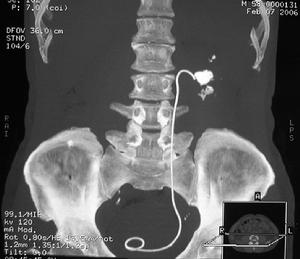

輸尿管結石輸尿管結石的正確診斷不僅是肯定有無結石,還要確定結石的大小、位置,兩側腎的功能和腎積水的程度,有無感染等。典型的腎絞痛與血尿是診斷的重要線索。在疼痛發作時肋脊區有壓痛、叩擊痛。女性輸尿管下端較大的結石能在陰道穹窿處觸及。 90%以上的輸尿管結石在尿路平片上可被顯示,草酸鈣顯示最佳,但需與腹腔淋巴結鈣化、盆腔內靜脈石、闌尾內糞石和骨島角相鑑別。靜脈尿路造影主要了解結石的部位和腎功能與有無積水,必要時行大劑量尿路造影及放射性核素腎圖>放射性核素腎圖檢查,均能進一步了解腎功能情況。膀胱鏡檢查與輸尿管插管在結石處受阻,並拍平片鈣化陰影在導管的同一平面,即能肯定輸尿管結石的診斷。陰性結石用空氣為對比劑作逆行造影攝片,則可顯示結石的存在。另外CT及B型超聲檢查有助於對X線平片不顯影結石的診斷。